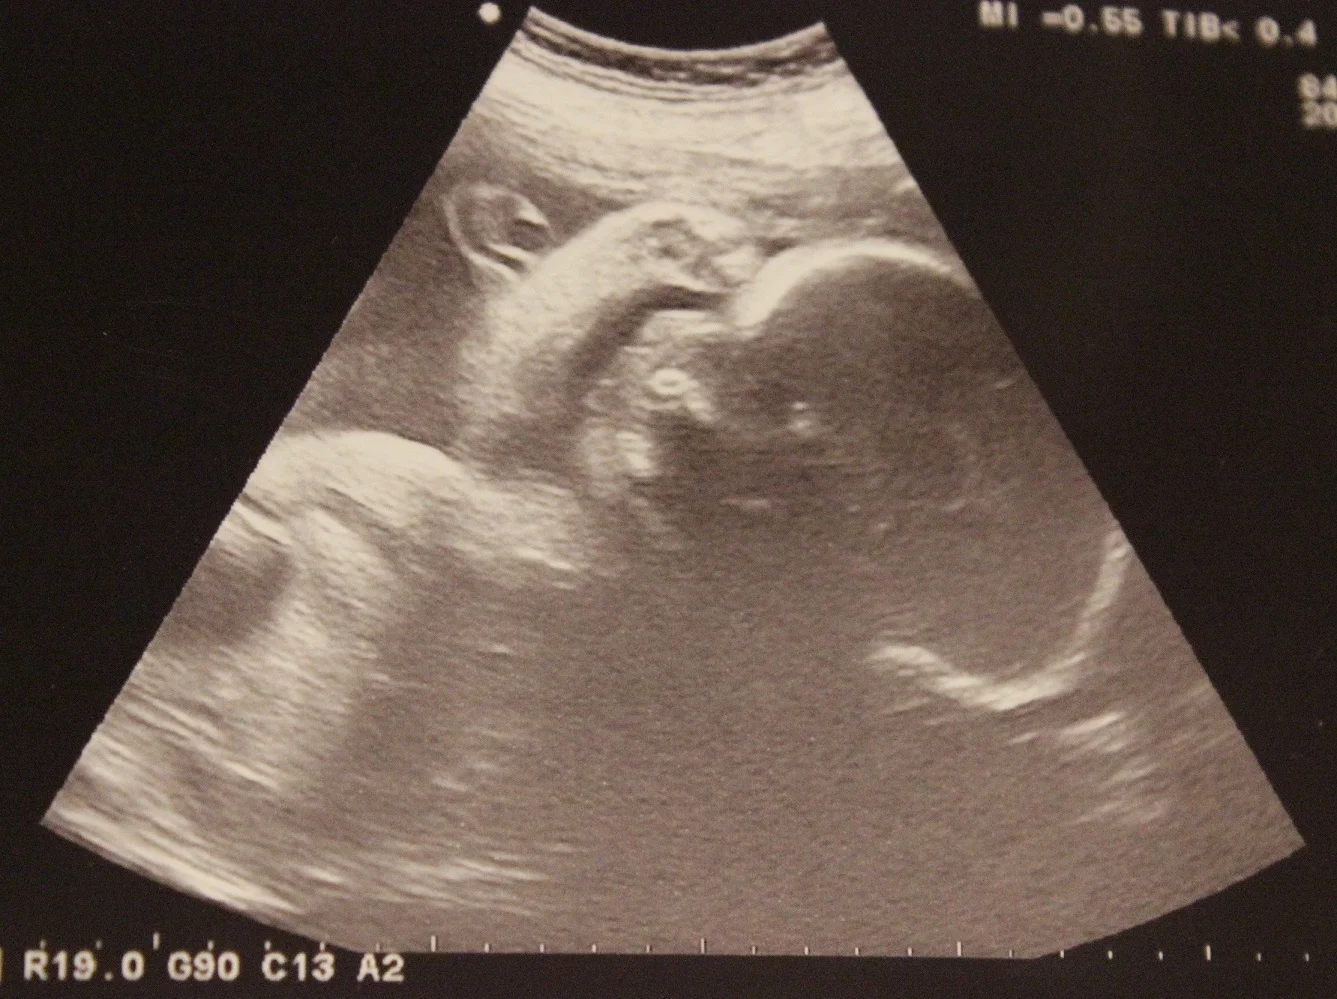

Admittedly, I am wound a little tightly this pregnancy. Paranoia about something going wrong coupled with my lack of quality sleep makes it harder for me to step back, take a deep breath, and tell myself "everything is fine -- chill the heck out."